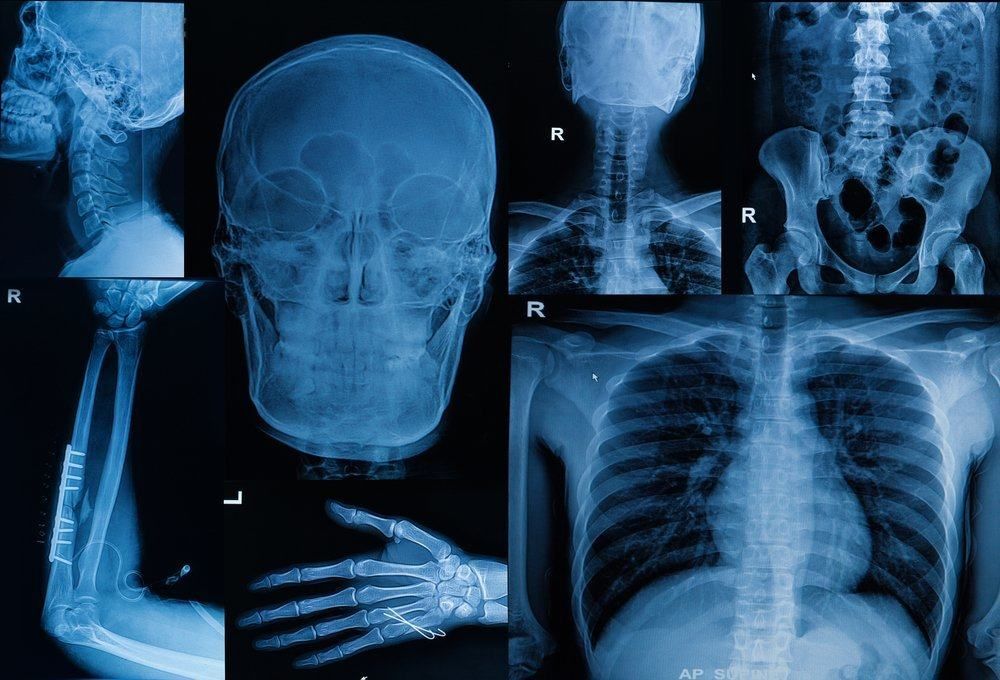

Mengenal Empat Jenis Penyakit Tulang yang Langka

Anda mungkin sudah familiar dengan penyakit tulang seperti osteoporosis. Tapi, perlu Anda ketahui bahwa di dunia ini ada banyak penyakit tulang yang langka. Contohnya seperti, osteogenesis imperfecta (OI), melorheostosis, chordoma, dan malignant fibrous histiocytoma (MFH). Meskipun merupakan penyakit tulang yang langka, penyakit tersebut sudah sering terdeteksi dalam tubuh manusia. Oleh karena itu, mari kita lihat lebih lengkap mengenai keempat penyakit tulang yang langka berikut ini.